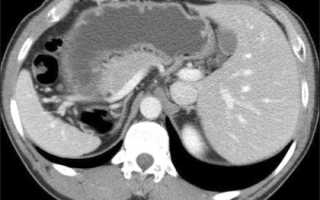

Процедура спиральной компьютерной томографии органов брюшной полости (СКТ ОБП) начинается с подготовки пациента в кабинете радиолога. Пациент располагается на специальном столе, который плавно перемещается через кольцевой аппарат – компьютерный томограф. Рентгеновский источник излучает небольшие дозы радиации, а детекторы улавливают проходящие лучи, создавая трехмерное изображение. Одной из ключевых особенностей СКТ ОБП является использование контрастного вещества, вводимого внутривенно, что позволяет лучше визуализировать сосуды и ткани, делая патологии более заметными.

| Что исследуется | Печень, желчный пузырь, поджелудочная железа, селезенка, почки, надпочечники, крупные сосуды, лимфоузлы | Оценка состояния этих органов, поиск опухолей, воспалений, камней, кист |

СКТ (спиральная компьютерная томография) органов брюшной полости включает в себя детальное сканирование таких структур, как печень, желчный пузырь, поджелудочная железа, селезенка, почки, кишечник и сосуды, а также лимфатические узлы и окружающие ткани. Исследование позволяет выявлять различные патологии, такие как опухоли, воспалительные процессы, травмы и другие аномалии.